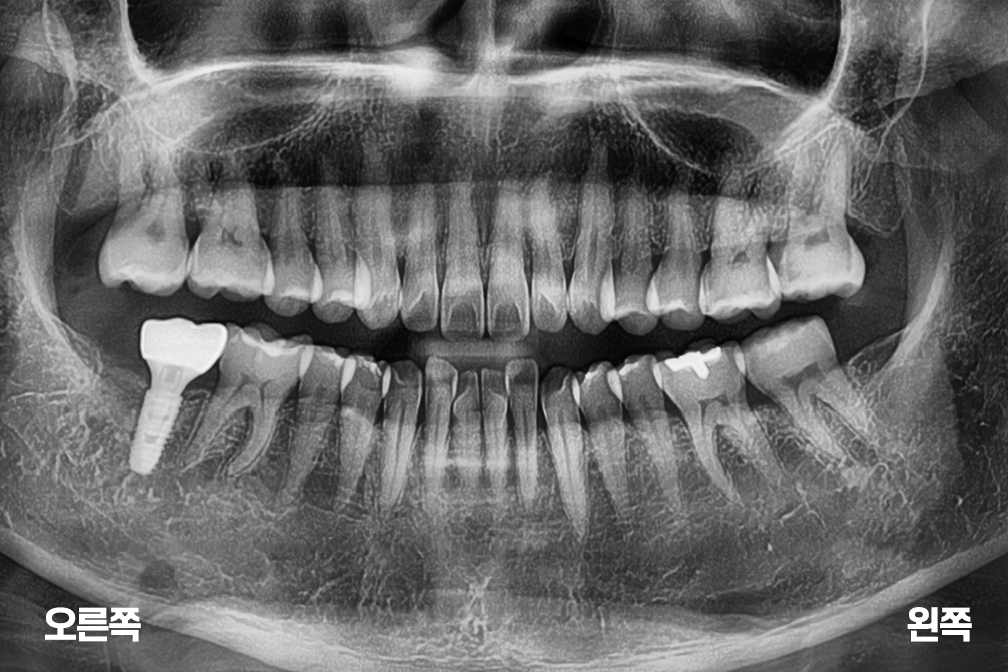

임플란트 오른쪽 아래 어금니 임플란트

Before 2025년 8월 19일